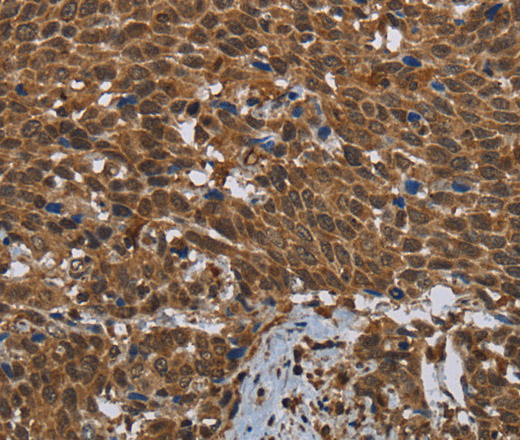

поликлональное антитело от производителя Elabscience к Glucokinase (GCK) источник — кролик предназначено для детекции целевого антигена в биологических образцах. Продукт характеризуется подтвержденной реактивностью к человек, мышь, крыса.

Антитело валидировано для методов: IHC. Подходит для научных исследований в области иммунологии, клеточной биологии и молекулярной диагностики.